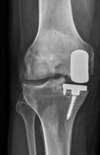

même patient prothèse médiale en place / vue de face

Une prothèse unicompartimentale du genou est formée de plusieurs parties :

Un implant fémoral qui va remplacer le cartilage usé du fémur sur sa partie interne ou externe, cet implant fémoral est ajusté au fémur et se fixe à l’os par un ciment acrylique ou par impaction seule

un implant tibial, qui va remplacer le cartilage usé du tibia sur sa partie interne ou externe, ajusté au tibia et fixé à l’os par vis ou ciment (résine) La prothèse laisse en place les attaches musculaires et les ligaments interne et externe du genou, le ligament croisé antérieur.